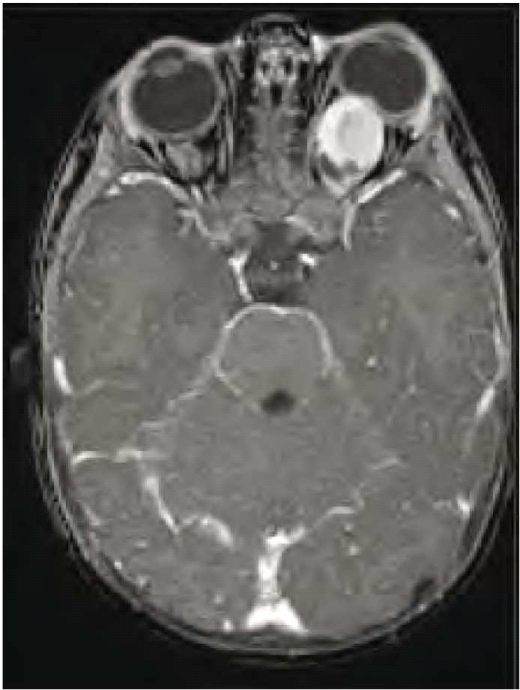

גליומות של המערכת האופטית

גליומות של המערכת האופטית מתפתחות בכ-15% מחולי נוירופיברומטוזיס מסוג 1 ועשויות לערב כל חלק של הנתיב האופטי, לרבות עצבי הראייה, כיאזמה (Chiasm), מסילות הראייה (Optic tracts) ומסלולי הראייה בתוך המוח. גידולים אלה מאובחנים לרוב בשנים הראשונות של החיים (בממוצע בגיל 4) ומתבטאים קלינית בירידה בחדות הראייה, פגיעה בשדות הראייה ולעתים בבלט עין (Proptosis) ובהתפתחות מינית מוקדמת במקרים של מעורבות תת-רמה (Hypothalamus). כיוון שילדים קטנים בדרך כלל אינם מתלוננים על ירידה בראייה, בדיקת עיניים תקופתית היא חובה בקרב הילדים החולים או חשודים כחולים בנוירופיברומטוזיס מסוג 1. במקרה של סימנים אובייקטיביים (Objective) של פגיעה במערכת הראייה [ירידה בחדות הראייה, סימנים של ניוון (Atrophy) של עצבי הראייה, פגיעה בשדה הראייה] יש צורך בבדיקת הדמיה בתהודה מגנטית של המוח וארובות העיניים (תמונה 5). אין כל הצדקה לשלוח ילדים לבדיקת טומוגרפיה ממוחשבת (CT, Computed Tomography) של הראש. מבחינה היסטולוגית, גליומות של המערכת האופטית הינן אסטרוציטומות פילוציטיות (Pilocytic astrocytoma), בעלות דרגת ממאירות נמוכה (1 WHO). ברוב המכריע של המקרים אין צורך בביופסיה והאבחנה נעשית על סמך המידע הקליני וההדמיתי. בדרך כלל, לגליומות של המערכת האופטית מהלך קליני שפיר. הן יכולות לגרום לפגיעה משמעותית בתפקוד הראייה בעיקר בעשור הראשון של החיים. בהמשך, גדילתן לרוב נעצרת ותפקוד הראייה נשאר יציב. במיעוט המקרים הגידולים גדלים בקצב גבוה ועלולים לפגוע בצורה קשה בראייה, עד כדי התפתחות של עיוורון מוחלט. הטיפול באותם מקרים כולל שימוש בתרופות כימיות (לרוב Vincristine ו-Carboplatin) עם נטייה להימנע משימוש בקרינה. התערבות ניתוחית נעשית במקרים של בלט עין קשה או לחץ תוך גולגולתי מוגבר בלתי נשלט.